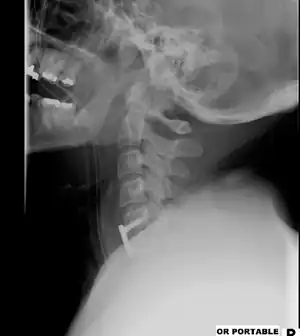

| Illustration depicting a surgical discectomy | |